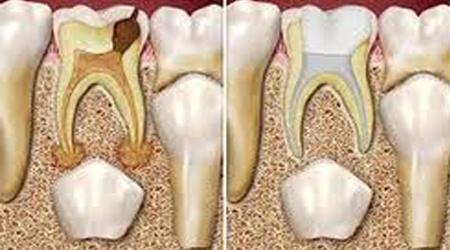

ROOT CANAL TREATMENT 4500-6000 70-90

• Root Canal Treatment